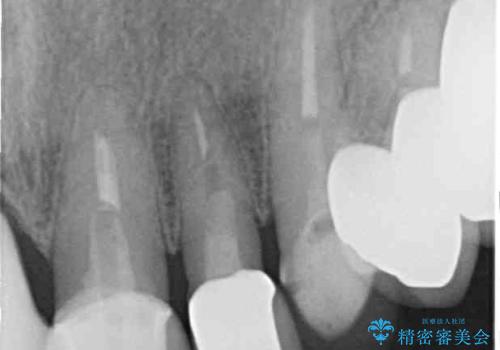

- 治療途中で装着していた仮歯汚れてしまい、恥ずかしいとのことで来院された患者様です。

土台の金属色が透けて見えてしまうため、ファイバーコアに置き換えた上で、オールセラミッククラウンにて補綴することとしました。